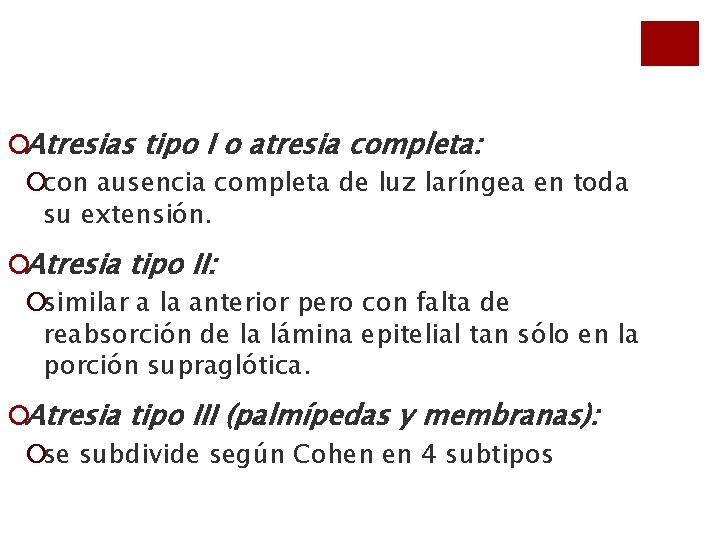

¡Atresias tipo I o atresia completa: ¡con ausencia completa de luz laríngea en toda su extensión. ¡Atresia tipo II: ¡similar a la anterior pero con falta de reabsorción de la lámina epitelial tan sólo en la porción supraglótica. ¡Atresia tipo III (palmípedas y membranas): ¡se subdivide según Cohen en 4 subtipos